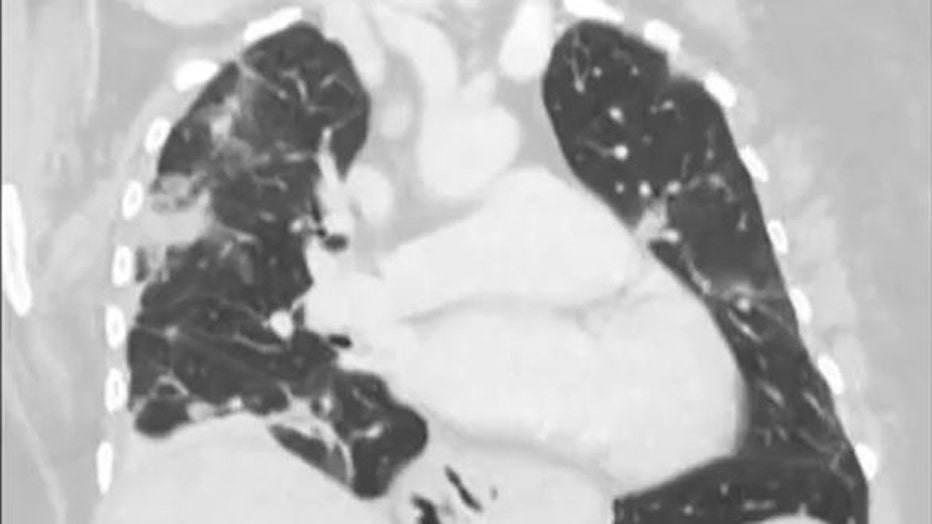

Doctors removed a worm "still alive and wiggling" from a woman's brain. (Credit: Australian National University via Storyful)

The woman had been admitted to the hospital after experiencing forgetfulness and worsening depression over three months. Scans showed changes in her brain.

A year earlier, she had been admitted to her local hospital in southeast New South Wales state with symptoms including abdominal pain, diarrhea, a dry cough and night sweats.